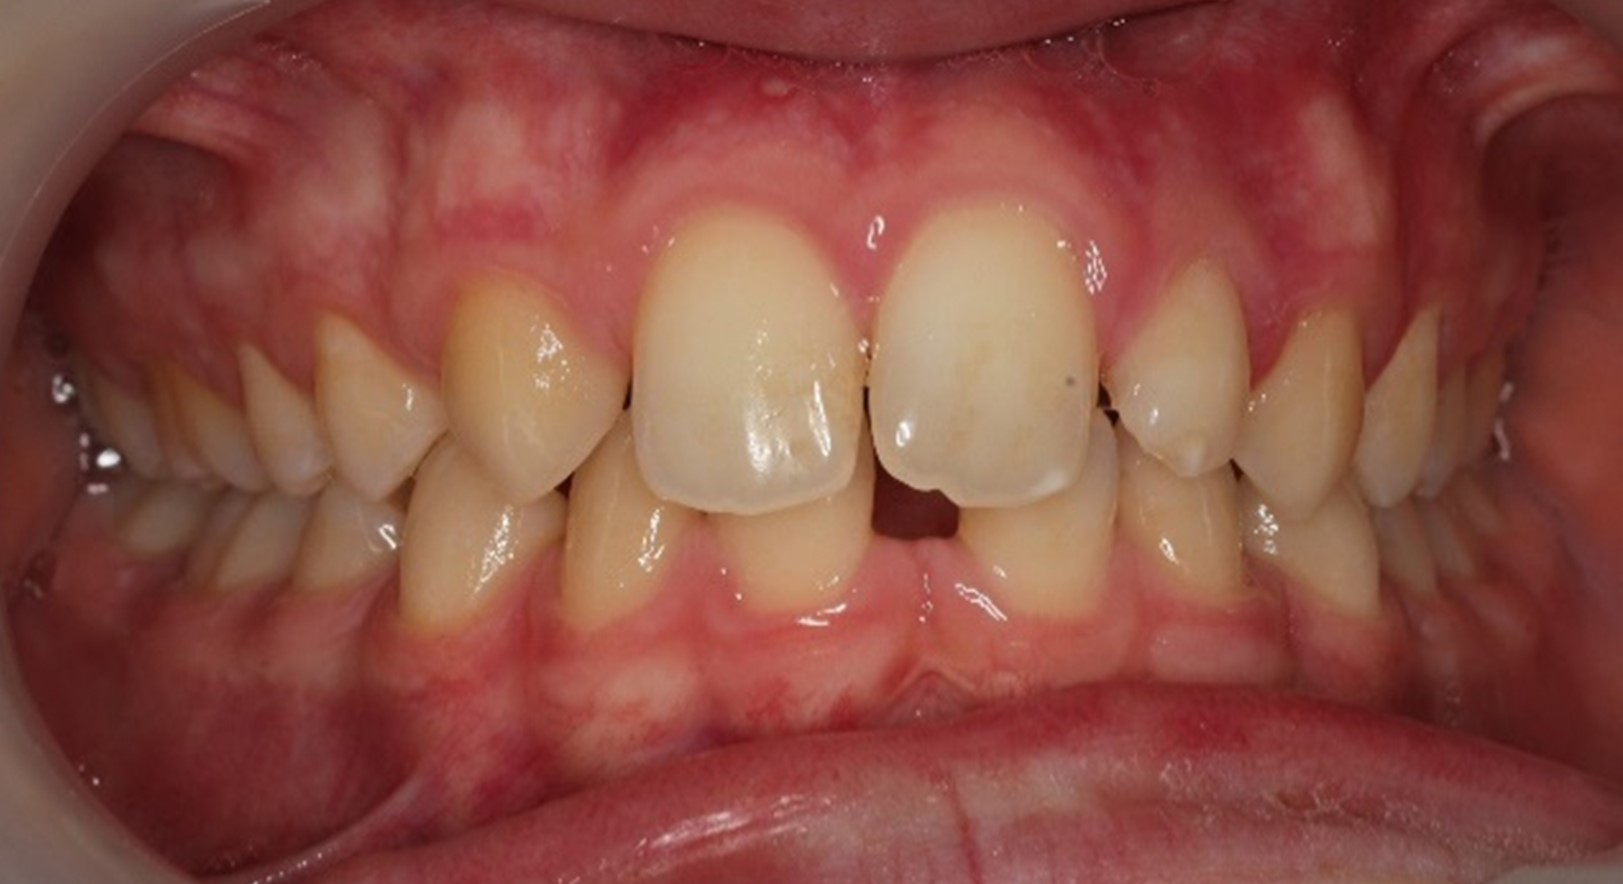

Skeletal Class II due to mandibular retrognathia, proclination of maxillary incisors, narrow arch creating a V-shaped arch, agenesis of 12, 31, 41, hyperdivergent facial pattern, moderate deep bite (2 mm), increased overjet (9 mm), asymmetric canine and molar Class II due to mandibular deviation to the left, maxillary midline deviation related to agenesis of 12, distal rotation of 35 and 45, and pronounced lower curve of Spee.

Stimulate mandibular growth, reduce overjet, correct Class II relationships, level the curve of Spee, manage space opening for agenesis of 12, 31, and 41, recenter midlines, improve oral function.

After 6 months:

Overjet reduced from 9 mm → 4 mm

Clear improvement in labial competence, nasal breathing, and tongue function.